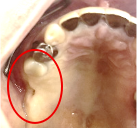

Before

※赤丸を抜歯しました。

After